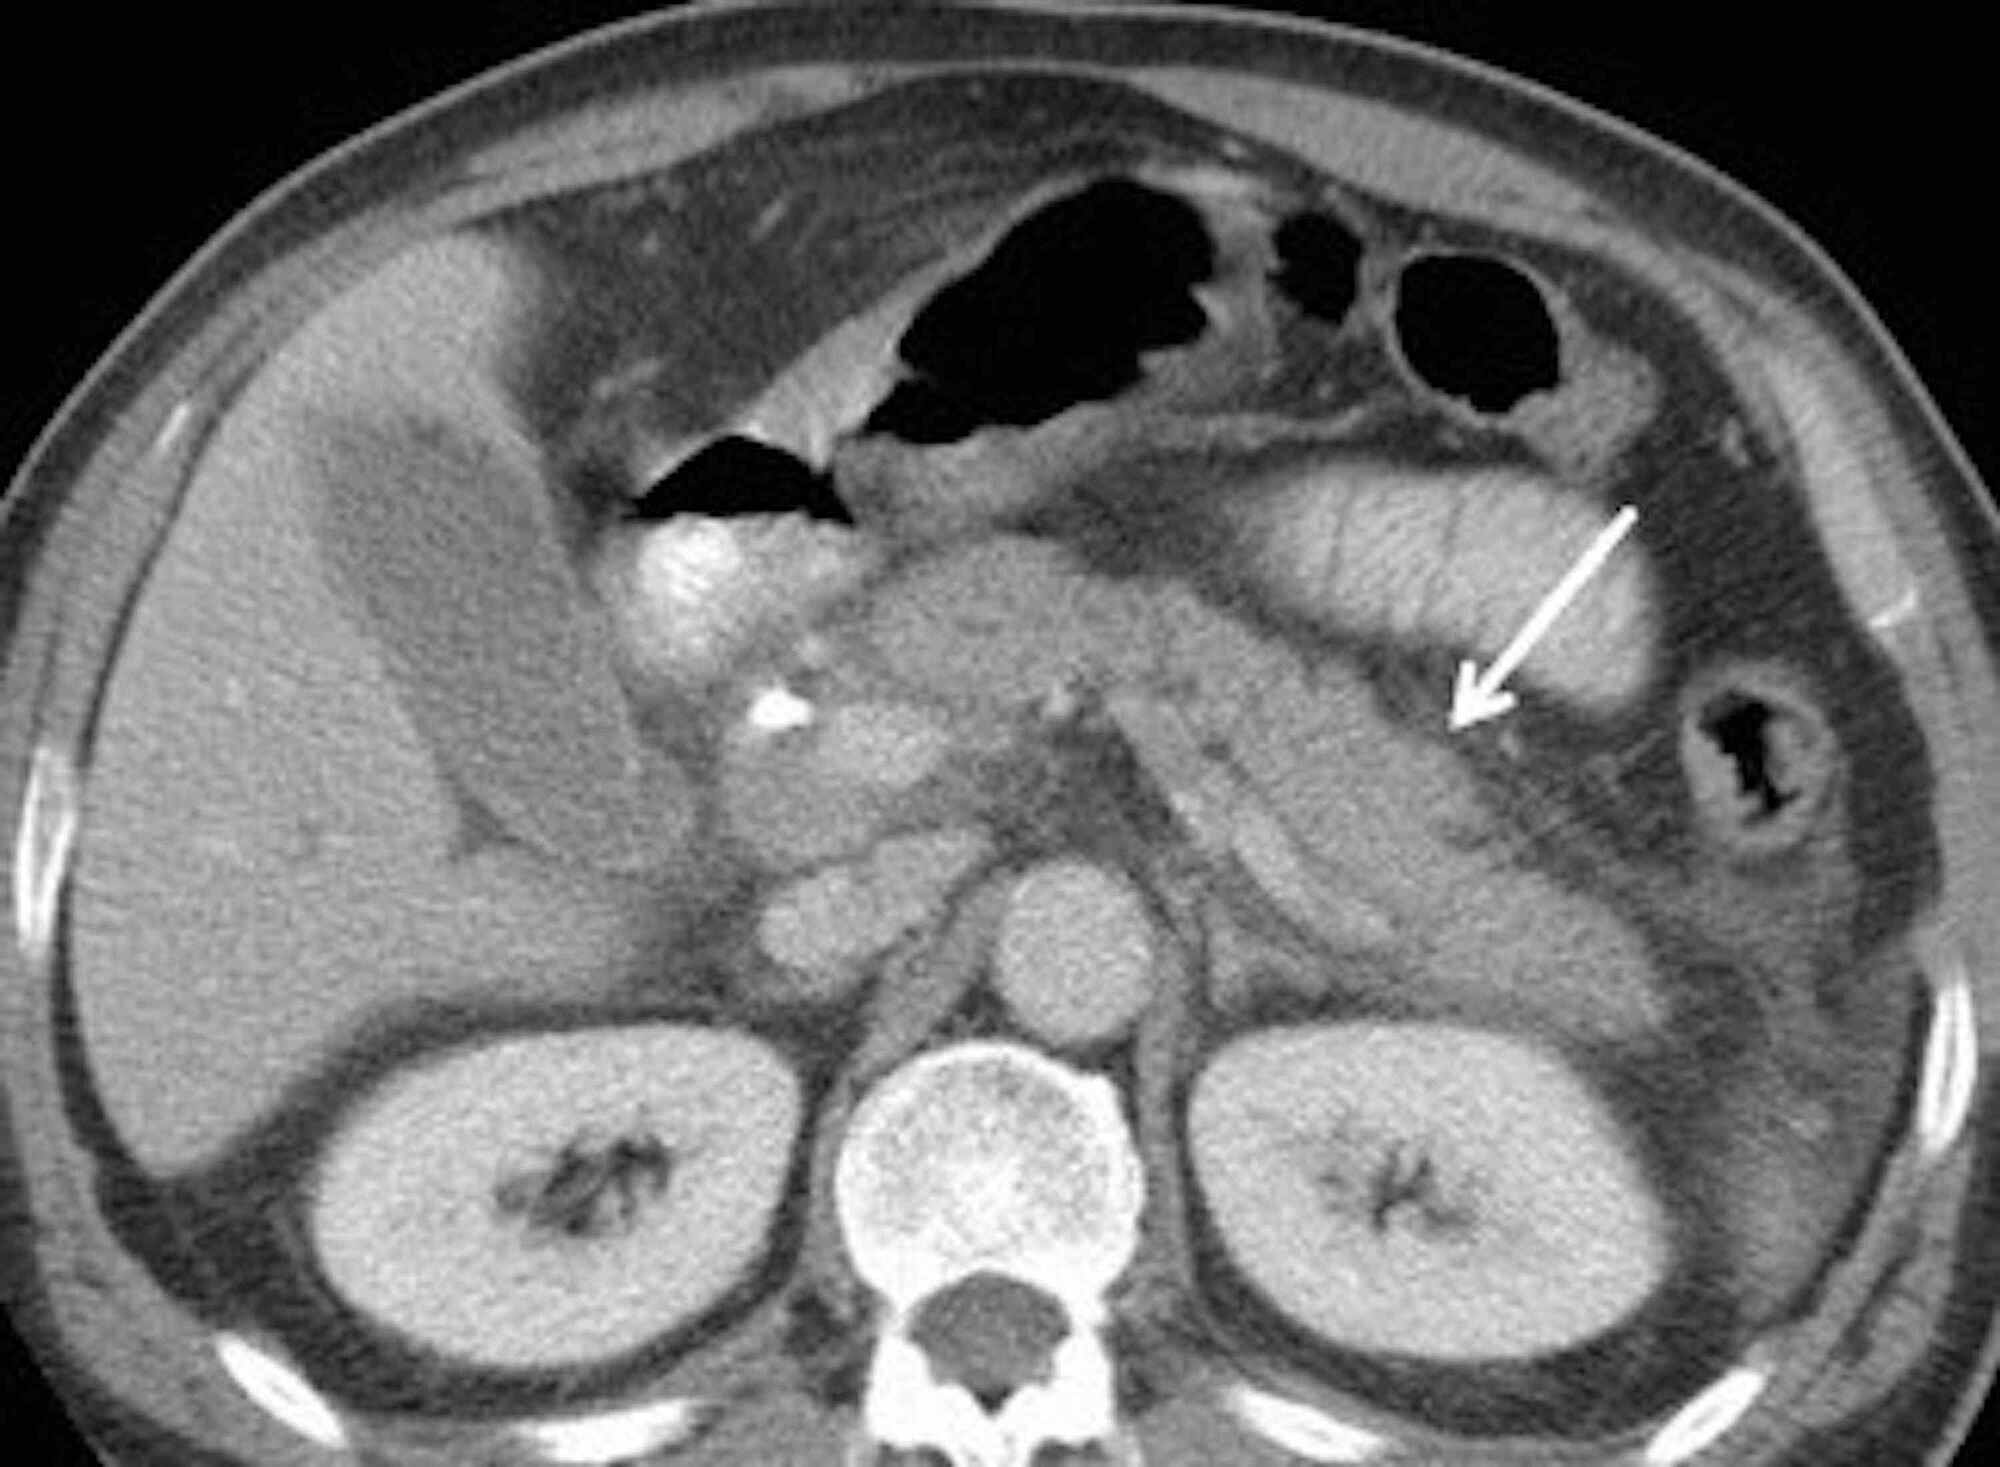

Cureus A Case of Severe Acute Pancreatitis Secondary to COVID19 Is Pot Bad For Your Pancreas cannabis use has been steadily rising in the united states and can have multiple adverse effects, including. acute pancreatitis correlated with increased cannabis use in 18 patients. patient services often receives questions about how medical marijuana can be used when fighting. introduction and background. cannabis use is emerging as a rare and overlooked cause of. Is Pot Bad For Your Pancreas.